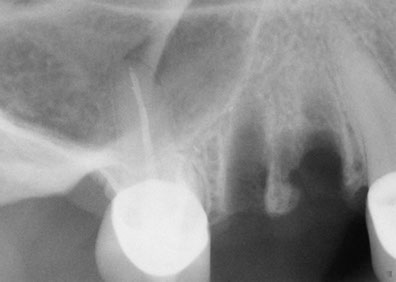

Una solución rápida y segura para hacer posible la instalación de implantes dentales

Fue Philip Boyne, quien en 1960 utilizo por primera vez la técnica Caldwell-Luc, empleada para corregir la falta de espacio maxilo-mandibular elevando la Membrana Sinusal en la zona de molares y premolares, colocando en la base del seno un injerto compuesto por hueso particulado o corticoesponjoso autógeno (que se origina o engendra a sí mismo ) para el relleno de esta cavidad ósea, con la llegada de los implantes de titanio radiculares, se observó que muchas zonas maxilares posteriores, eran inadecuadas en altura y anchura ósea, por lo que se requirió injertar hueso dentro del seno maxilar para hacerlas adecuadas receptoras de implantes. La elevación de senos, es una técnica quirúrgica necesaria cuando no hay suficiente hueso, se añade hueso entre el maxilar superior y los senos maxilares, que son un anexo de las fosas nasales por lo que están en ambos lados de la nariz, la forma y el tamaño de este seno varían en cada persona y con el paso de los años se va haciendo más grande (inadecuado para implantes dentales).

Esta técnica es empleada en cirugía dento-alveolar, oncología y traumatología, con el objeto de  dar arreglo a  un defecto óseo craneofacial etc. La elevación de seno es una solución segura a través de la cual es posible la instalación  de los implantes dentales osteointegrados, dando como resultado estética y funcionalidad a la dentadura, este procedimiento es también conocido como Sinus Lift.

Esta técnica esta recomendada en aquellos casos donde es imposible colocar implantes dentales con la longitud óptima en la parte posterior del maxilar superior ya que en  esta región se posee generalmente una calidad ósea Tipo III ó IV y por esto es necesario utilizar implantes de una longitud mínima de 10mm y del mayor diámetro posible.